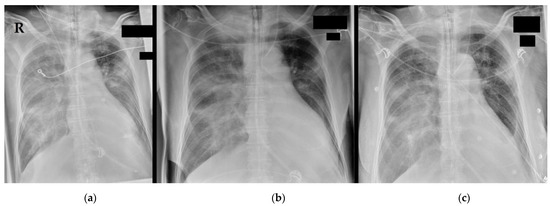

2. Surroundings and Materials

3.4. Further Diagnostics

3.5. Final Diagnosis and Deterioration